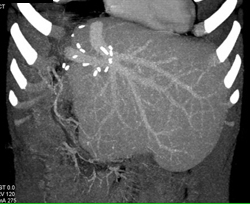

Liver Metastases From Bladder Cancer